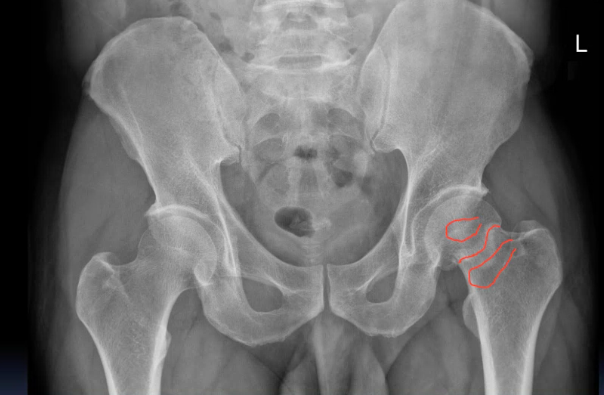

An 48 year old man presented to the ED with 3-day history of left hip pain after falling in the shower. He was struggling to walk. On examination his left leg was a little shorter than the right and slightly laterally rotated.

What action would you take? Justify your course of action / investigation / management!